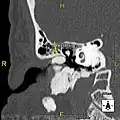

Normal ear canal

-

Exostosis in ear canal

The normal ear canal is approximately 7 mm in diameter and has a volume of approximately 0.8 ml (approximately one-sixth of a teaspoon).[5] As the condition progresses, the diameter narrows and can even close completely if untreated, although people generally seek help once the passage has constricted to 0.5–2 mm due to the noticeable hearing impairment. While not necessarily harmful in and of itself, constriction of the ear canal from these growths can trap debris, leading to painful and difficult to treat infections.